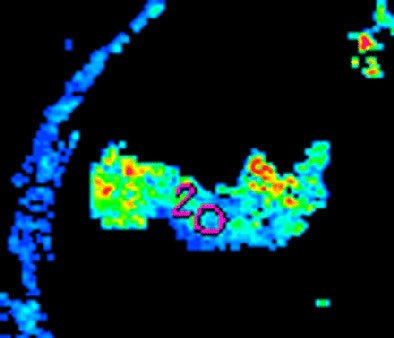

The researchers measured blood volume, blood flow, and permeability-surface area product for 40- or 120-mm2 circular ROIs placed at the tumor edge and center and around the manually outlined visible tumor, the authors wrote. The ROI analysis was repeated by two observers in different subsets of patients to assess intra- and interobserver variation.

The position and size of the ROI had a major impact on measurements, the team reported. All three measures -- blood volume, blood flow, and permeability-surface area product -- were significantly higher at the tumor edge versus the center in both 40- and 120-mm2 ROIs (p < 0.001).

| Morphologic image (arrow, above) shows cecal cancer. Corresponding blood volume parametric maps show 40-mm2 ROI at tumor edge (below) and center (bottom). Images republished with permission of the Radiological Society of North America. Goh V, Halligan S, Gharpuray A, Wellsted D, Sundin J, Bartram CI. Quantitative assessment of colorectal cancer tumor vascular parameters by using perfusion CT: Influence of tumor region of interest. Radiology. 2008;247(3):726-732. |

"These findings are concordant with morphologic data that have considered the distribution of vessels in colorectal cancers," they wrote. "For example, findings in a study of the three-dimensional vascular structure of colorectal tumors assessed by using microvessel corrosion casting and electron scanning micrography indicated elegantly that tumor vessels demonstrate a zonal distribution irrespective of tumor size. Vascularity decreased from the tumor edge to the center, with the tumor center poorly vascularized. Vessels in the tumor center also appeared compressed and elongated when they were compared with vessels (which were dilated) in areas of greater vessel density."